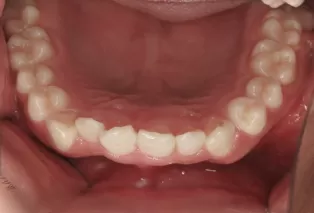

Photos intra-orales